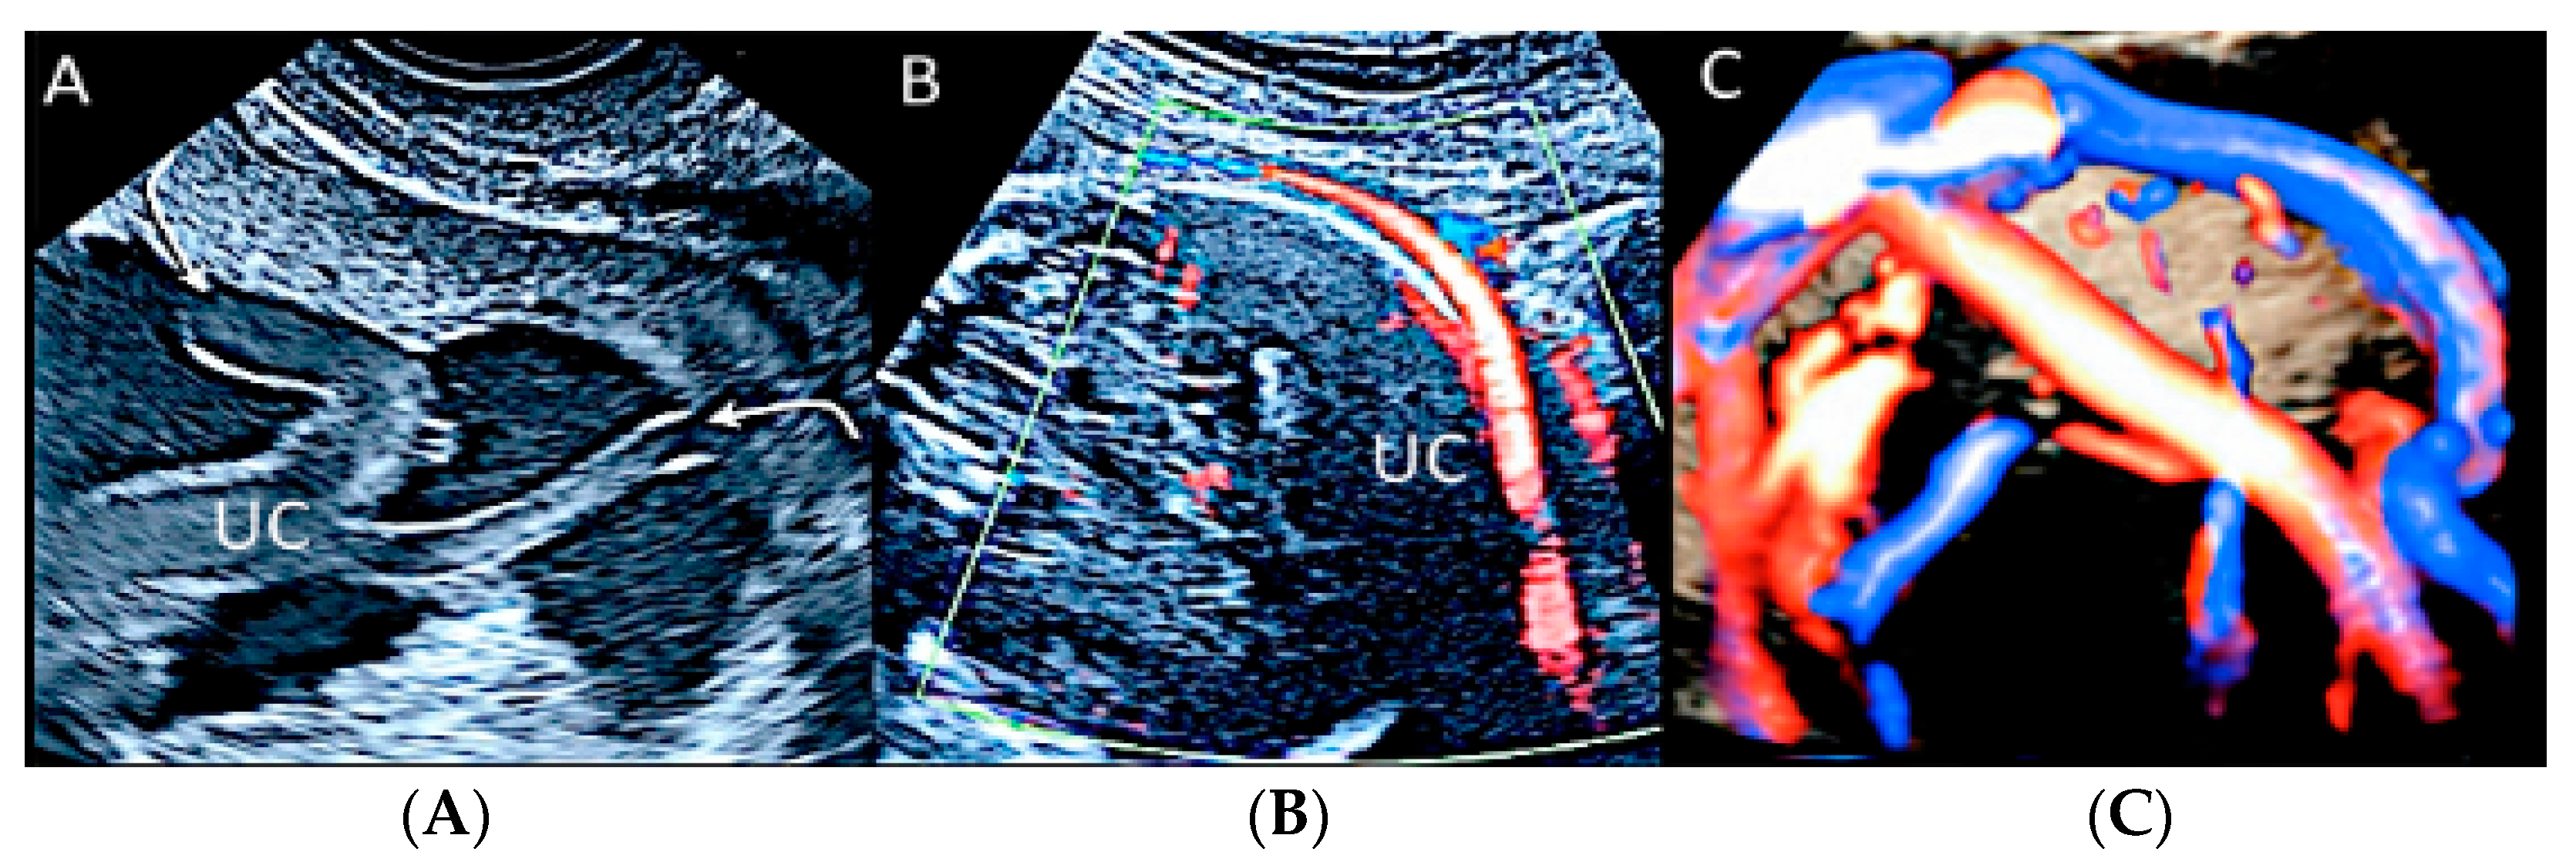

Figure 22.

Pregnancy at 20 weeks gestation. Two-dimensional ultrasound (A), color Doppler (B) and four-dimensional STIC with color Doppler ultrasound (C). In velamentous insertion, the umbilical cord vessels (UC) diverge from each other, inserting into the membranes not supported by Wharton jelly, before entering the placental tissue (curved arrows, figure on the left) (A). The diagnosis of velamentous cord insertion is made through color Doppler ultrasound by the discovery of splayed umbilical vessels at the periphery of the placenta (B). It may be associated with vasa praevia (Type I) when umbilical vessels running through the fetal membranes are close to the internal cervical os (figure on the center). Four-dimensional STIC with color Doppler ultrasound (C) image showing the “mangrove sign” for velamentous cord insertion.